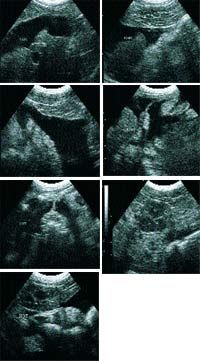

Thorough abdominal ultrasound is performed with the cat positioned in dorsal recumbency.

There is a large amount of free fluid accumulated within the abdominal cavity. The liver shows a uniform echogenicity in its parenchyma. No masses noted within the liver parenchyma. The gall bladder is mildly distended, and its walls are not thickened or hyperechoic. The gall bladder does contain some sludge material. The spleen or a limb of the pancreas is enlarged, contains irregular margins, and is echobright in its parenchyma. The left and right kidneys are similar in size, shape and echotexture. No masses or calculi were noted in either kidney.

Image 3 - 9.